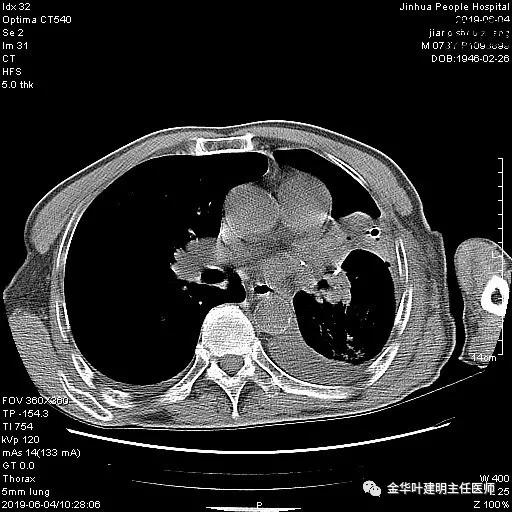

考虑左侧大量胸腔积液,遂进一步胸部CT检查:

以上是肺窗表现,下面为纵隔窗影像: